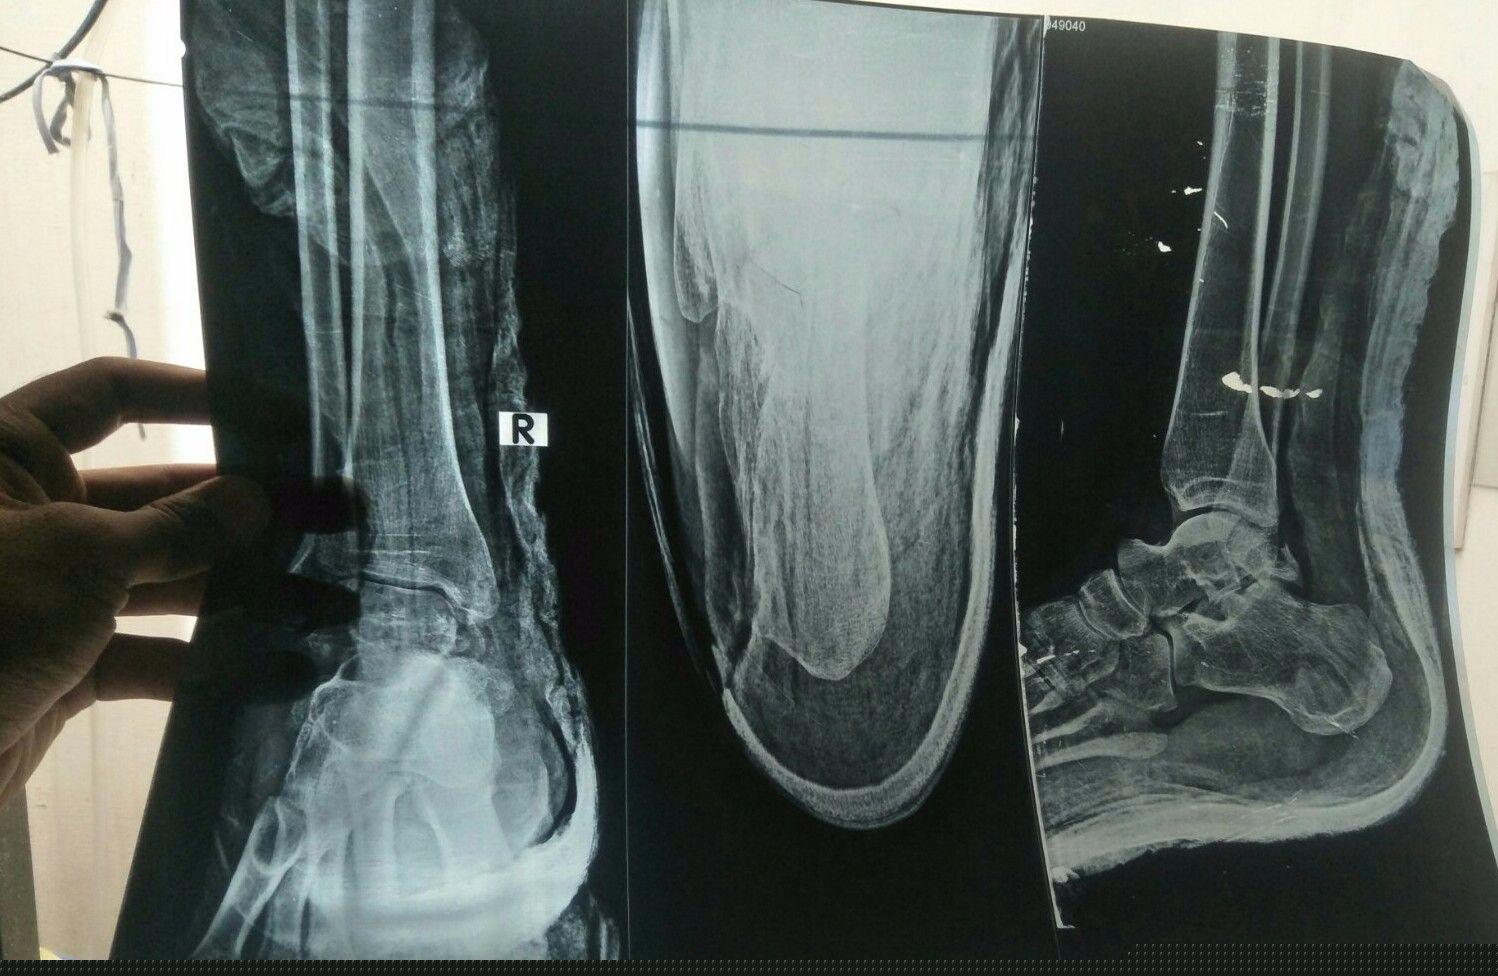

Koi dctr senior dctr guide kry ye xray h.. Ye oprate bgair ni jur skhti plaster ky Sth ?? Plz anser or kb tuk oprate ky bd chl skhey ga kitni rest h Ya oprate he ho ga to kesy ho ga cut lgye ga kia daly gye ?? Or hadi jor kah rhy h jur jaey gi oprate ky bgair b.. Plz guide

need clear xray

More X-rays views required. These X-rays are not good and not helpful

Can be managed in cast. No surgery required

cannot comment without physical examination. This patient requires 3D CT reconstruction images before any decision to made.

Show Ap view also to be confirmed cast n not weight bearing can also heal

need to examine the pt and ap view also required for further management

Plz post AP view of this x ray as well.... Then it can be commented

Hi, you need to get MRI to decide about treatment. Thanks